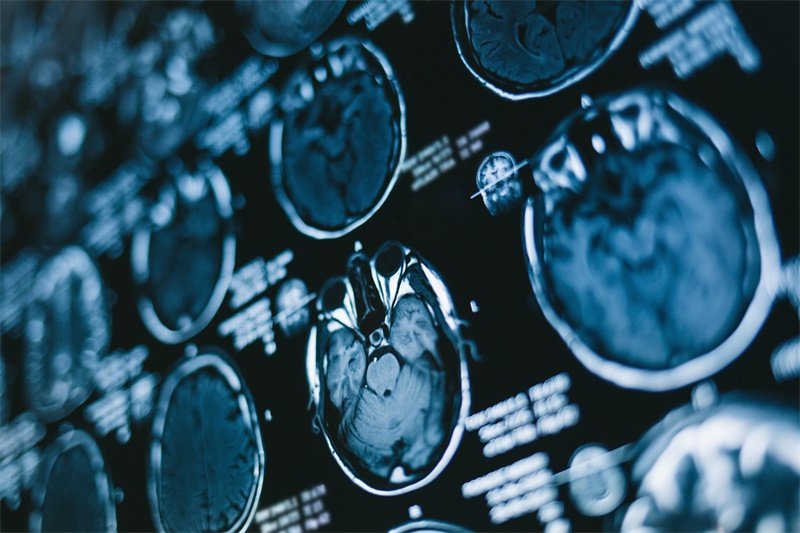

在神经外科领域,蝶鞍占位是一个至关重要的概念。蝶鞍是位于颅底的一块特殊骨结构,葱包着重要的腺体和神经。蝶鞍占位的病变可以由多种原因引起,包括肿瘤、囊肿、感染等。这些病变可能对周围结构产生压迫,导致患者出现诸如视力变化、内分泌失调等症状。了解蝶鞍占位的相关疾病及其影响,对于患者及其家属做出早期识别与管理至关重要。

蝶鞍占位通常是指在蝶鞍区域发生的结构性病变。这个区域被称为“蝶鞍”(sella turcica),形状类似于马鞍,其内主要包含垂体腺。由于蝶鞍的解剖特殊性,其病变往往会严重影响身体的多个系统。

蝶鞍位于颅底,外观如马鞍,主要由蝶骨形成。其内侧有垂体腺,是内分泌系统的一个重要组成部分。此外,靠近蝶鞍的还有视神经、海绵窦等重要结构,这些组织的正常功能对维持身体健康至关重要。